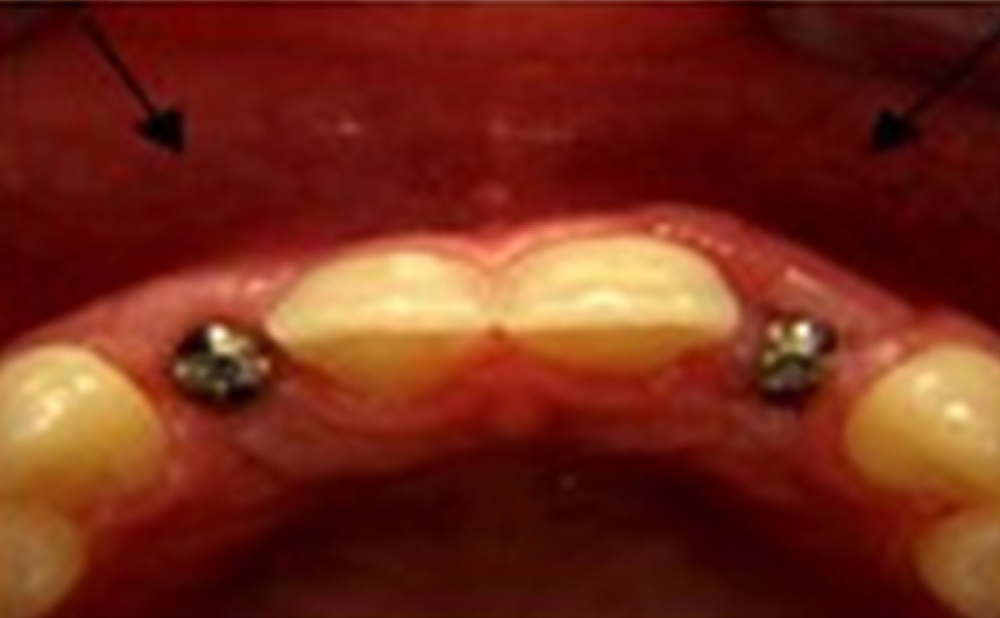

In these cases, a bone graft is performed to increase the ridge height and/or width. Ridge augmentation makes future implant placement possible with attractive, natural results.

Bone grafting is generally done after the doctor’s initial examination and before placing the implant base. This work aims to strengthen the jaw’s bone tissue because the base of the dental implant must be placed in this bone.

Dental implant is a multi-step process. The most crucial step is placing a screw-like metal piece inside the jawbone. This part is called the implant base. During the surgery, the doctor shaves a bit of the jawbone and places the implant base inside it.